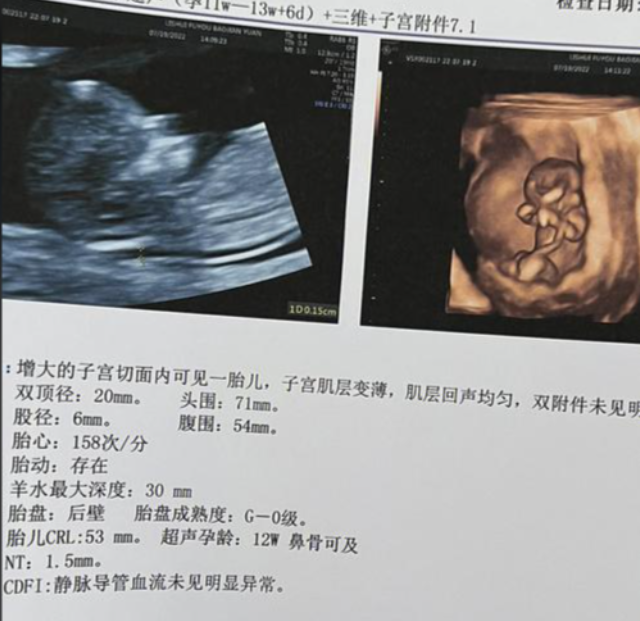

网上流传通过怀孕13周的Nt单子可以看出胎儿性别,但是很多孕妈妈都不知道具体应该怎么看。下面为大家整理了13周已生男宝的nt单子,大家可以对照看一下。

1、一般认为NT值在正常范围内,大于1.5毫米话,就说明孕妇怀的是男孩儿,因为相对来说男性的皮肤要比女性的更厚一些,因此颈后透明带的厚度也会比女孩子更厚;

2、如果胎儿的Nt值在正常范围内的同时低于1mm的话,就说明怀的是女宝宝,女宝宝的皮肤相对来说会更加薄一些,因此颈后透明带也会比较薄。

以上就是通过Nt单子上具体数据来判断生男生女的方法,当然由于每个宝宝的情况不同,因此这种方法也并不是非常准确的,除了通过数据来看以外,还可以通过Nt报告单中胎儿的姿势以及图像进行判断。